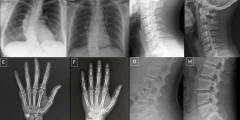

الأشعة السينية المزيفة: تحديات جديدة أمام دقة التصوير الطبي